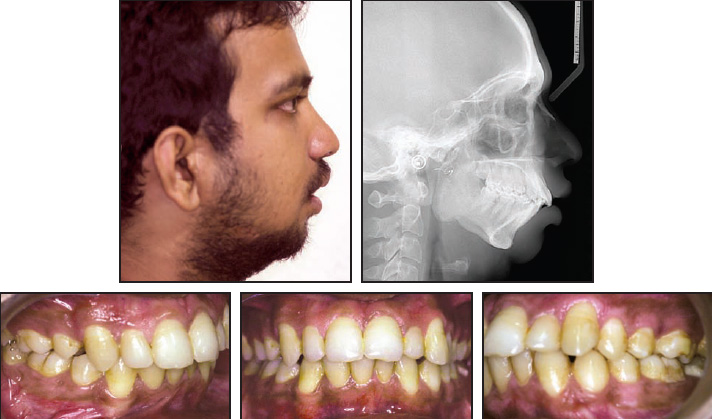

An 18-year-old male presented to the Department of Oral and Maxillofacial Surgery with problems including reduced mouth opening, loud snoring, excessive daytime somnolence, morning headaches, and an impaired ability to concentrate (Fig. 1). He had been treated for bilateral TMJ ankylosis with costochondral grafts 10 years previously and a bilateral coronoidectomy five years previously. He was referred to the Department of Orthodontics.

Fig. 1 18-year-old male patient with severe craniomandibular deformity, retrognathic mandible, facial convexity, and crowding in both arches before treatment.

On clinical examination, the patient exhibited excessive sleepiness, inability to focus and concentrate, reduced cognitive function, and a pale, sickly appearance. He was likely to doze off in the dental chair even when waiting for a few minutes. Extraoral examination showed facial asymmetry, with the chin deviated to the right. The profile was severely convex, and the lower jaw appeared severely retrognathic in both the horizontal and vertical dimensions. Mouth opening was limited to 15mm, making it difficult to take impressions.

Intraoral evaluation revealed proclination and crowding of the upper and lower anterior teeth, with an overjet of 12mm, an overbite of 5mm, a constricted upper arch with a tendency toward crossbite, and a buccal crossbite of the upper left second molar. The mandibular left lateral incisor was lingually displaced and was extruded well above the occlusal plane.

Radiographs showed the defective condylar joint and evidence of past surgery. All teeth were present except for the upper right and both lower third molars. The lower right second premolar was impacted. Cephalometric analysis confirmed a severe facial convexity, a retrognathic mandible, a deficient chin and lower facial height, and proclined upper and lower anterior teeth (Table 1).